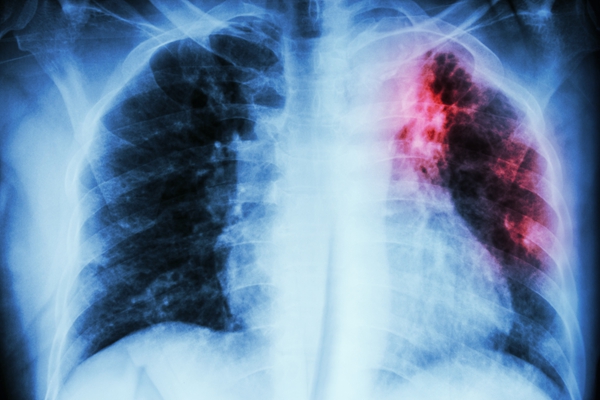

Pulmonary Tuberculosis

Pulmonary Tuberculosis . Chest X-ray : interstitial infiltration at left upper lung due to Mycobacterium Tuberculosis infection